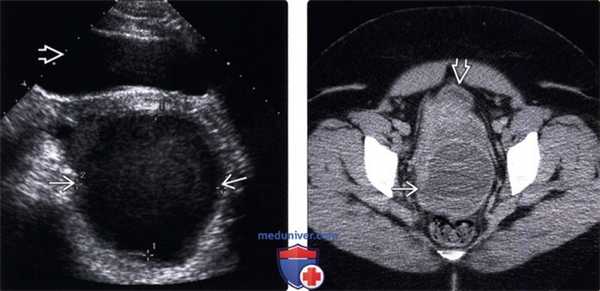

(Левый) Пациентка с диабетом после дилатации и кюретажа. На поперечном УЗ срезе таза в дугласовом пространстве позади мочевого пузыря определяется толстостенный абсцесс.

(Правый) У той же пациентки при КТ с контрастным усилением подтвержден толстостенный абсцесс. Мочевой пузырь пуст.

(Левый) У ребенка, недавно перенесшего оперативное вмешательство по поводу осложненного аппендицита, определяется однокамерное скопление жидкости, содержащее источники эхосигналов.

(Правый) У этого же пациента при КТ с контрастным усилением подтверждается наличие скопления жидкости; этот метод позволяет более детально рассмотреть толстую контрастную стенку и прилегающие структуры.